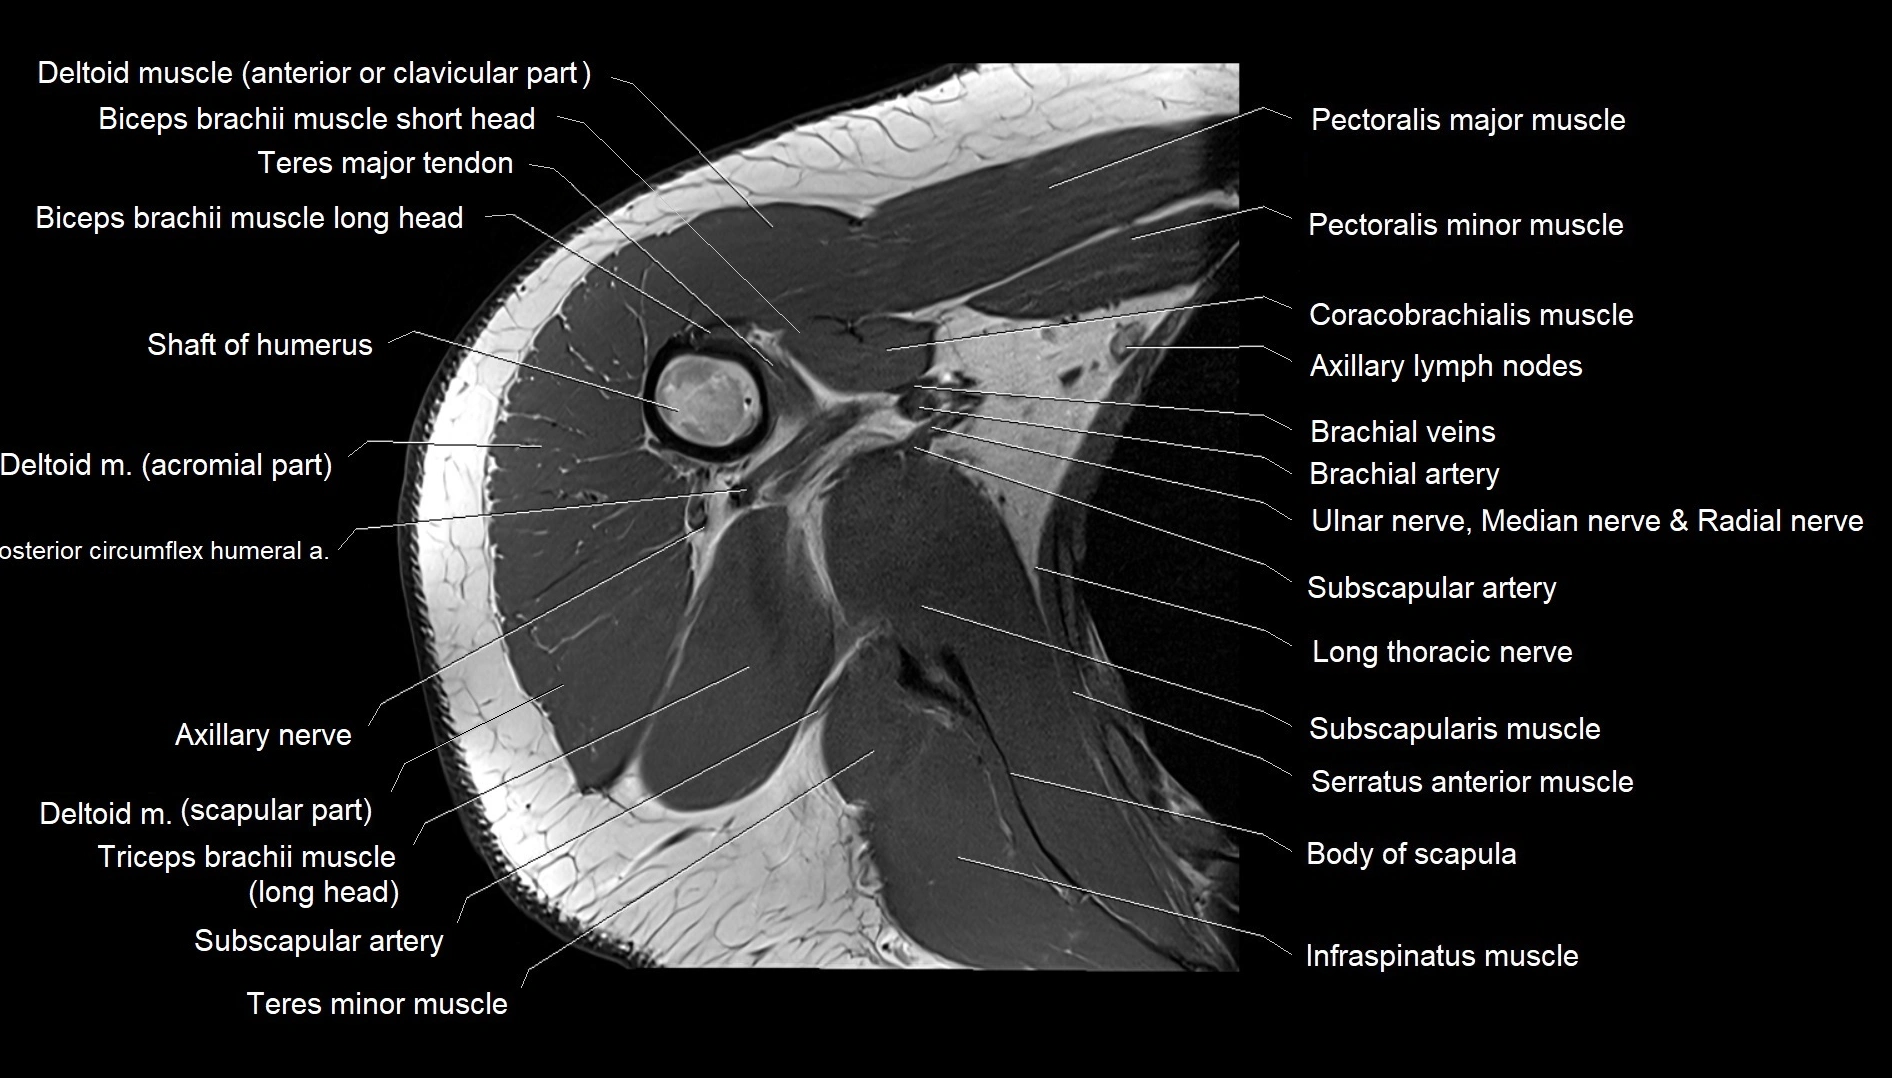

CT image

image